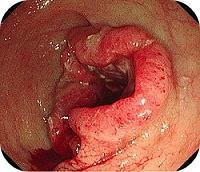

- 대장내시경검사

대장내시경검사는 특수한 카메라인 내시경을 항문으로 삽입하여 대장 내부를 직접 들여다보는 방법이다. 요즘 사용하는 내시경은 유연한 튜브의 끝에 광섬유로 연결된 카메라가 달려 있다. 의사가 직접 출혈 부위와 병변의 표면을 관찰하고 조직 상태를 파악할 수 있으므로 대장 질환의 가장 정확한 진단법이다. 내시경검사와 동시에 조직검사(생검)을 하는 것도 가능하다. 짧은 시간만 작용하는 일종의 수면제를 정맥에 주사한 뒤 수면내시경(의식하 진정 내시경검사)을 시행하면 불편함 없이 검사를 받을 수 있다. 환자는 검사 전날 저녁 식사를 죽 등으로 가볍게 하고 하제를보용하여 대장 안에 남아 있는 분변을 모두 제거해야 한다.

대장내시경검사의 장점은 대장용종의 발견에 매우 민감하여, 발견된 용종을 즉시 제거할 수 있다는 점이다. 단점은 검사 전 대장정결이 필요하고 수면내시경이 아닐 경우 환자가 불편해 할 수 있으며, 암 등으로 대장 내강이 막혀 있으면 더 이상 검사를 진행 할 수 없다는 것이다.

다양한 방식의 진단방법이 있으나 제일 확실한 것은 대장내시경을 통한 생검(조직검사)이다. 대장암은 대장내시경을 통해 직접 보았을 때 암 인지 아닌지 알 수 있는 경우가 많아서 대장내시경만 꾸준히 받아도 조기 발견에 큰 도움이 된다.

용종 중에서도 암으로 변이하는 선종의 경우 80%정도는 5년에서 10년 정도의 장기간에 걸쳐서 암으로 변이하기 때문에 내시경만 몇 년에 한 번씩 받아도 조기에 제거할 확률이 커지기 때문에 50세이상부터는 적어도 3년에 한번 이상은 대장내시경 검사를 받아야 조기진단이 가능한 확률이 높아진다.

대장암의 진단은 대장내시경으로 최초로 발견되는 경우가 많다.

내시경상 육안으로 종양이 확인될 경우 즉시 조직을 체취하고 조직검사를 하여 암인지 여부를 확인 한다. 조직검사 결과 암으로 확진이 될 경우 암진단은 확정이 된다.